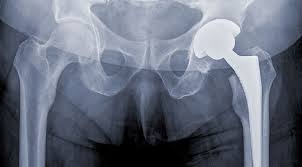

Arthoplasty is another name for hip replacement. This is a process that involves surgery of the deformed parts of the pelvis. Afterwards these removed parts of the hip are replaced with artificial hip parts that are referred to as prosthesis. All of us know about the working of the hip joint in our bodies. There is a ‘ball and socket joint’ in the hip that allows the hip to rotate in different directions. Because of this injury, both the ball and the socket of this joint are affected. Arthoplasty removes both of them and replaces them with artificial ball and socket to improve mobility of the individual.